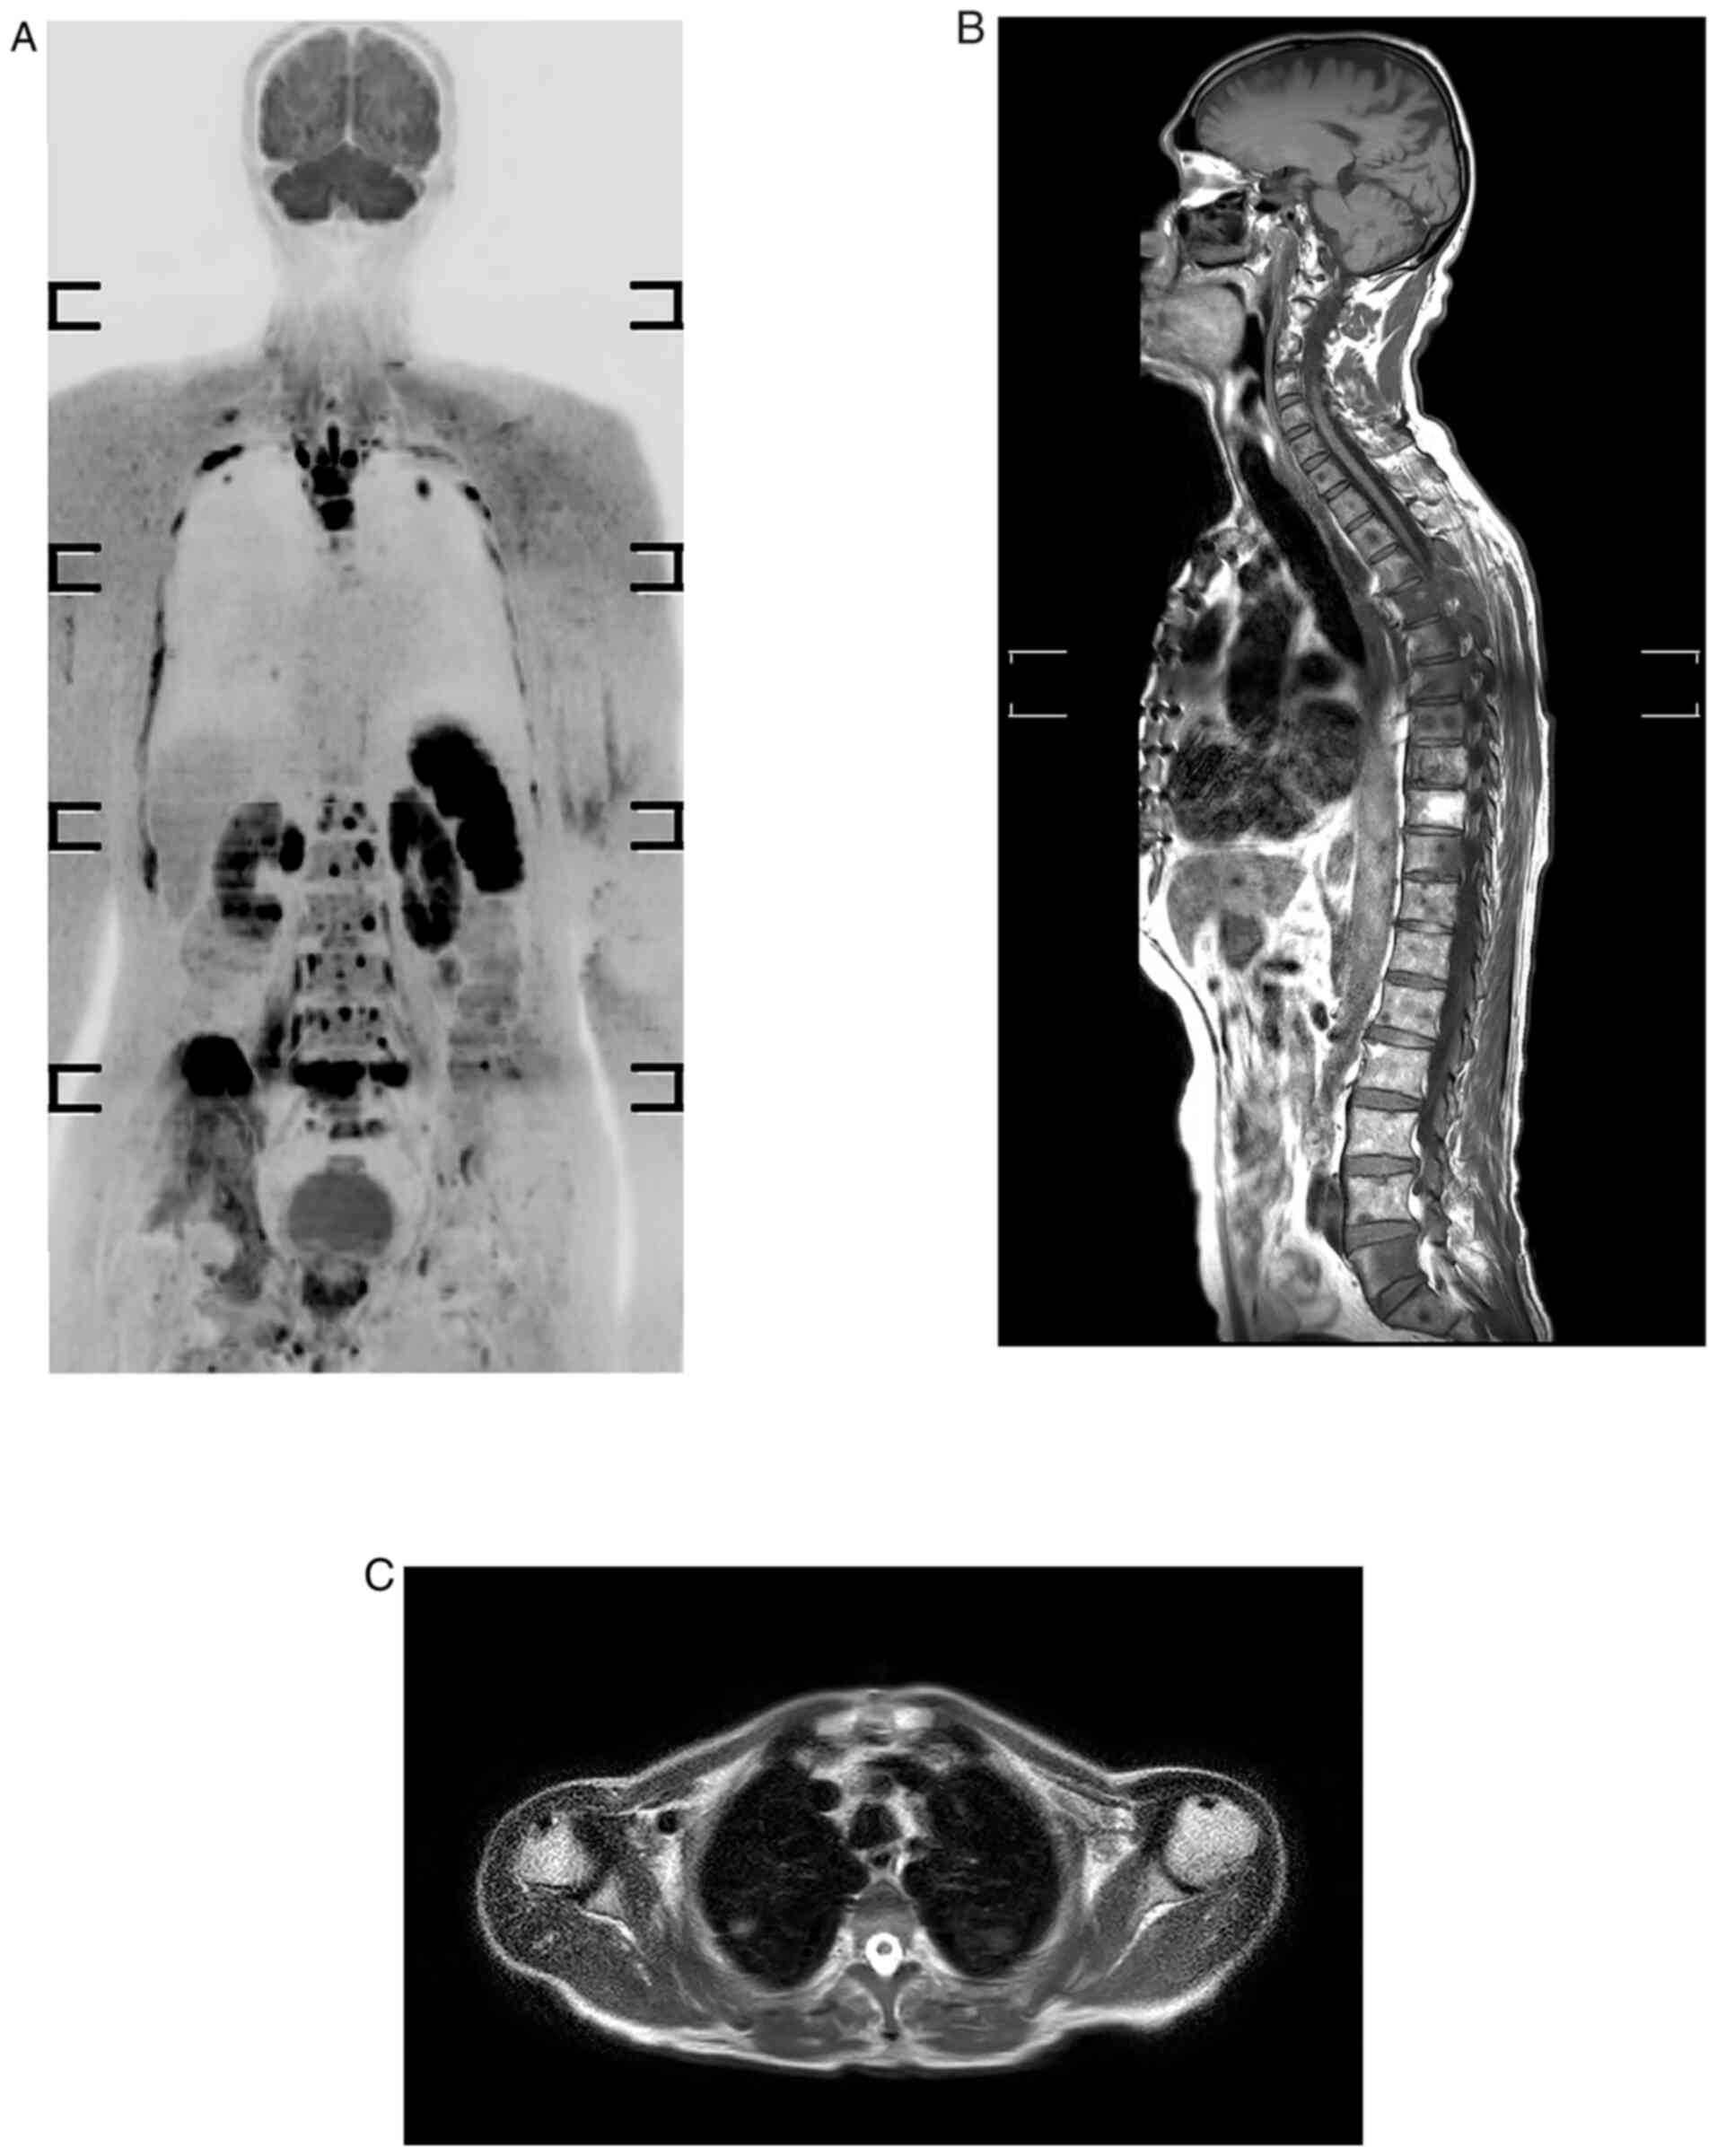

For the LNs, a region-based analysis was performed. A total of 258 areas were evaluated on 43 individuals. Lymphadenopathy was defined as any LN measuring >10 mm in the short axis diameter or any abnormal LN of any size that had newly appeared. WB-MRI verified 38 of the 258 LNs as positive, whereas histology confirmed 36. Two LN areas were first considered to be negative on imaging but turned out to be positive on histology. The presence or absence of metastases was determined in all skeletal areas. WB-MRI was used to evaluate 301 regions of the 43 patients, with 66 sites considered positive. The accuracy for detecting bone metastases was 100%. There were no false-positive or false-negative results for skeletal and visceral metastases. The sagittal plane is strongly recommended in oncology because spine curvatures may be responsible for partial volume effects that conceal certain lesion on coronal plane. In the current study, the accuracy for bone metastasis was 100%; this high result is explained by the efficacy of DWBIS and the provision of images in three orthogonal planes (Fig. 1).

Figure 1

Whole-body MRI of a 69-year-old male who developed prostate cancer presented with skeletal and lung metastases. (A) Inverted black-white coronal diffusion-weighted MRI with background body signal suppression sequence displaying multiple rib, vertebral and right iliac bone lesions, and also pulmonary lesions at upper lobes bilaterally. (B) T1-weighted image displaying hypointense dorsal and lumbar skeletal lesions. (C) Axial T2-weightedimage showing abnormal focal pulmonary lesions.

The study found that WB-MRI was 100% accurate in diagnosing skeletal and visceral metastases but only 98.45% accurate in diagnosing LN metastases. The sensitivity, specificity and accuracy of visceral, skeletal and nodal metastases are all provided in Table III.